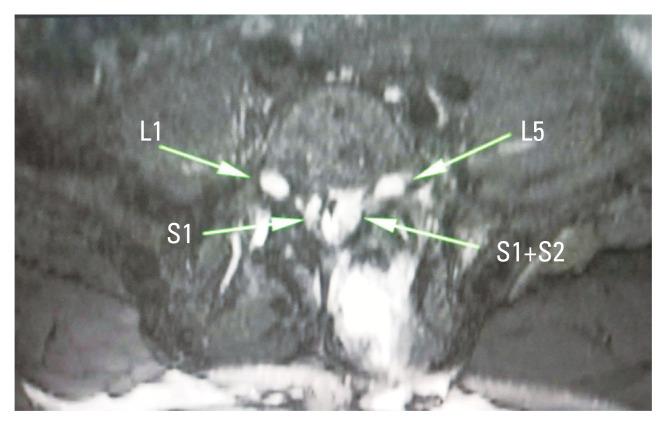

Conjoint nerve root (CNR) is an embryological nerve root anomaly that mainly involves the lumbosacral region. The presence of CNR during tubular discectomy raises the chances of failure in spinal surgery and the risk of neural injuries. Tubular discectomy can be challenging in the presence of CNR owing to limited visualization. Here, we present a technical note on two cases of L5-S1 disc prolapse in the presence of conjoint S1 nerve root that was operated via a minimally invasive tubular approach. Any intraoperative suspicion of CNR while using the tubular approach should prompt the surgeon to perform a thorough tubular decompression prior to nerve root retraction. In patients with a large disc, disc should be approached via the axilla because the axillary area between the dura and the medial boarder of the root is very easy to approach in the presence of CNR. Safe performance of tubular discectomy is possible even in the presence of CNR in the lumbar spine.

联合神经根(CNR)是一种主要累及腰骶部的胚胎学神经根异常。在管状椎间盘切除术过程中出现CNR会增加脊柱手术失败的几率以及神经损伤的风险。由于视野受限,在存在CNR的情况下进行管状椎间盘切除术可能具有挑战性。在此,我们介绍一份技术笔记,内容为两例存在联合S1神经根的L5 - S1椎间盘突出症病例,通过微创管状入路进行手术。在使用管状入路时,术中任何对CNR的怀疑都应促使外科医生在神经根牵拉之前进行彻底的管状减压。对于椎间盘较大的患者,应通过腋部入路处理椎间盘,因为在存在CNR的情况下,硬脊膜与神经根内侧边界之间的腋部区域非常容易进入。即使在腰椎存在CNR的情况下,进行管状椎间盘切除术也可以安全实施。